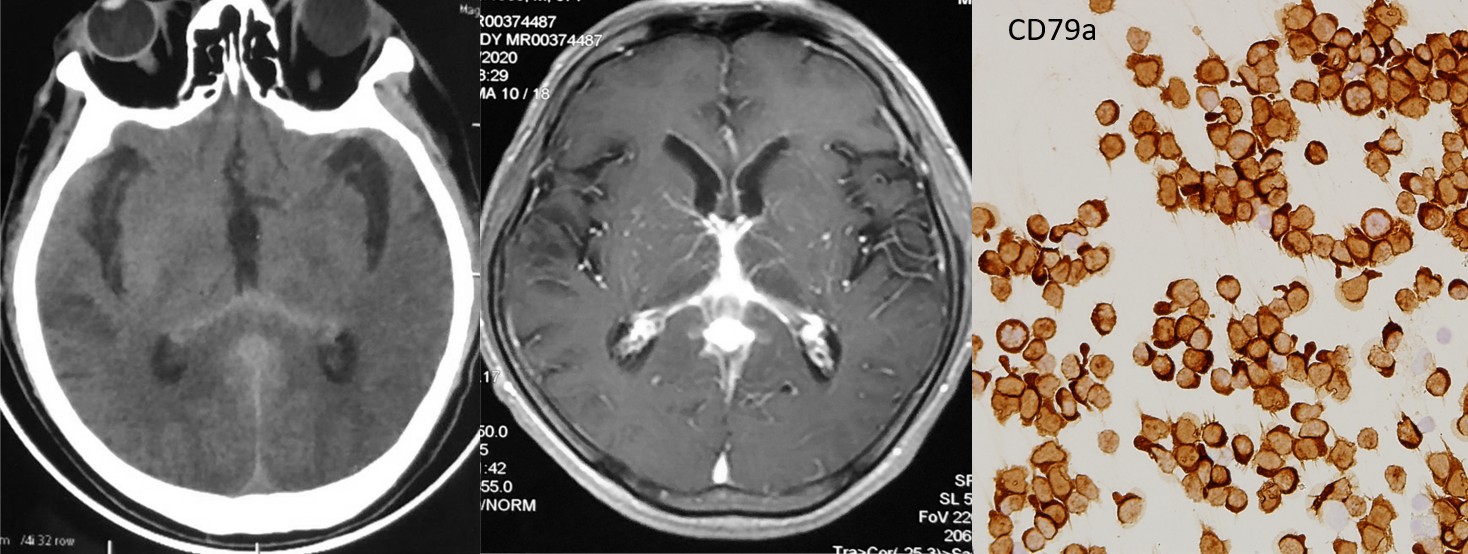

该患者,男,57岁,因“头晕、头痛7个月,加重3个月”来我院就诊。患者因颅脑CT显示后纵裂及第三脑室高密度病灶在当地绿帽社按“蛛网膜下腔出血”治疗,脑血管造影无阳性发现,后颅脑MRI平扫加强化显示除后纵裂明显强化外,胼胝体压部及双侧丘脑均有受累,遂来我院神经内科门诊,门诊以“颅内病变性质待查”收入神经内科西五病房。

在与神经内科邓小梅副主任技师和孙佳主管技师以及病理科沟通后,经患者知情同意后行腰穿并留取足量脑脊液送检,脑脊液常规瑞姬氏染色发现患者脑脊液细胞数高、细胞略大、有伪足且细胞核异形,于是用脑脊液室传统的玻片离心机制备了6张浓缩脑脊液脱落细胞学涂片,然后送至病理科,分染HE、Ki67、CD3、CD19、CD20和CD79a,Ki67阳性率约60%,CD20及CD79a(+),考虑B细胞淋巴瘤可能。请血液科赵川莉主任医师会诊并转入血液科,再次腰穿脑脊液脱落细胞送检流式细胞学检查提示大B细胞淋巴瘤,骨髓穿刺细胞学及骨髓活检病理未见淋巴瘤细胞,行PET-CT扫描未见中枢神经系统外病灶。综合上述所有检查,确诊原发性中枢神经系统弥漫大B细胞淋巴瘤,评估心脏功能后确认无治疗禁忌,给予“利妥昔单抗+大剂量甲氨蝶呤+伊布替尼”方案治疗,患者病情好转出院。